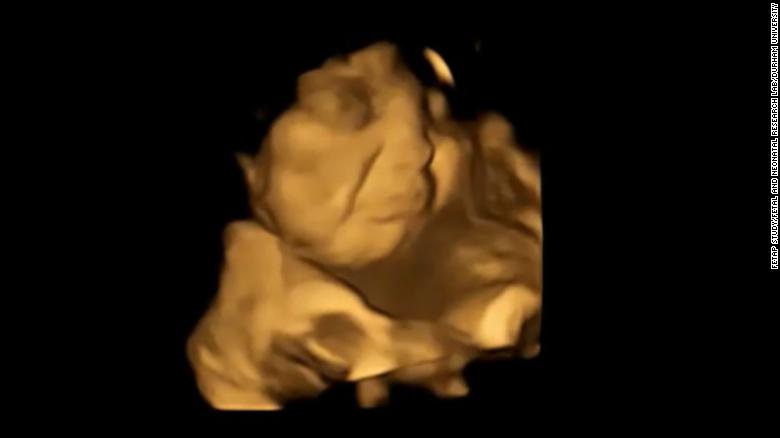

Зародиш, изложен на вкуса на къдраво зеле.

20 минути, след като изяждат капсулите, жените са подложени на 4D ултразвук, като крайния резултат е съпоставен с 2D изображения на зародишите.

Оказва се, че вероятността зародишът да е направил гримаса, сходна с тази на усмивка, е много по-висока в групата, консумирала моркови. Същевременно при тази с къдраво зеле повечето зародиши са направили физиономия, наподобяваща мръщене или плачещо личице.